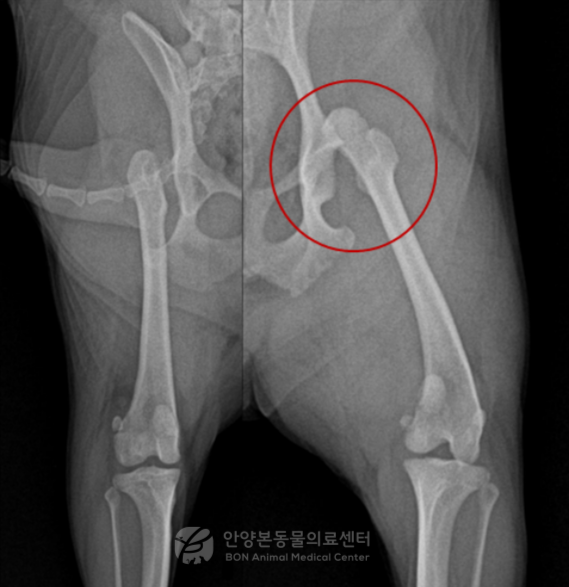

이번 환자는 7살령 포메라니안 중성화 수컷 강아지로 좌측 후지 파행을 주증으로 안양본동물의료센터에 내원했습니다. 보호자님 설명에 따르면 밤에 집 안에서 갑자기 돌다가 비명을 지른 뒤 좌측 뒷다리를 딛지 못하는 상태가 되었다고 합니다.

이 환자는 과거 반대쪽 다리에 대퇴골두절제술(FHNO)을 받은 병력이 있었습니다.

방사선 검사 결과 좌측 고관절 탈구와 퇴행성 관절 변화가 확인되었습니다.